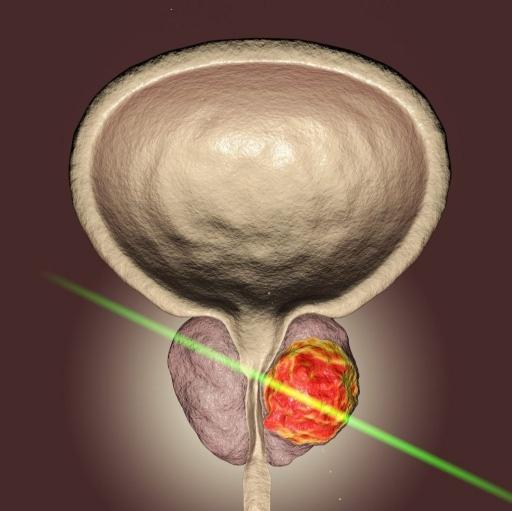

Cirugía láser de próstata y piedra, Laparoscopía urológica,

Riñones, Cáncer urogenital, Cirugía percutanea de cálculos, Endourología.

Láser para incontinencia urinaria sin cirugía, Termoablación de tumores.

Vasectomia y recanalización de deferentes, varicocele.

Cel. 9992 78 3333

antonioesqueda@hotmail.com www.urologoenmerida.com

Enfermedades de: Próstata, Riñones, Vejiga, Genitales, Infecciones urinarias, Litiasis urinaria, Disfunción eréctil, Infertilidad.

Cáncer de próstata